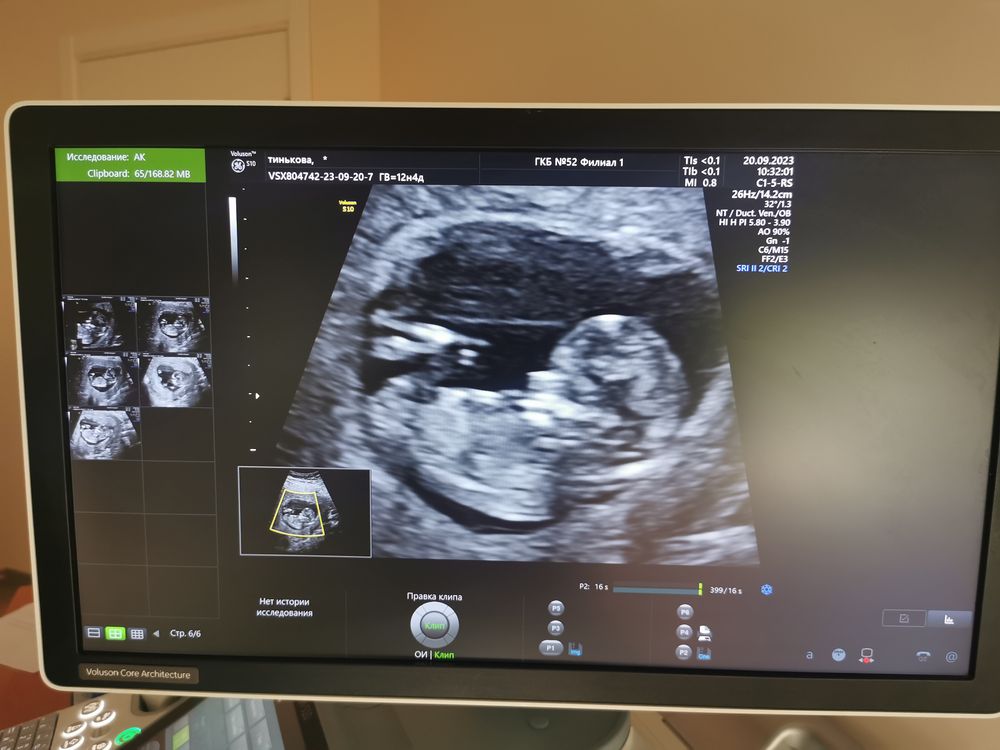

Виктория, ну у вас тут прям ноги широко и торчит отчётливо 👍👍👍🔥 мужик

13.10.2023

Анастасия , ну он почему то на всех узи это место выпячивает . Хвастается что ли 😀. Просто у меня фото более четкое , темнее . Поэтому так явно все видно